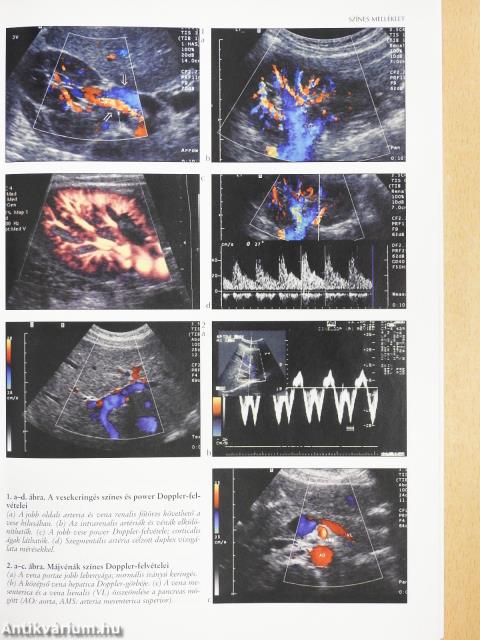

A vesekeringés duplex ultrahangvizsgálata60

A máj célzott ultrahangvizsgálata46